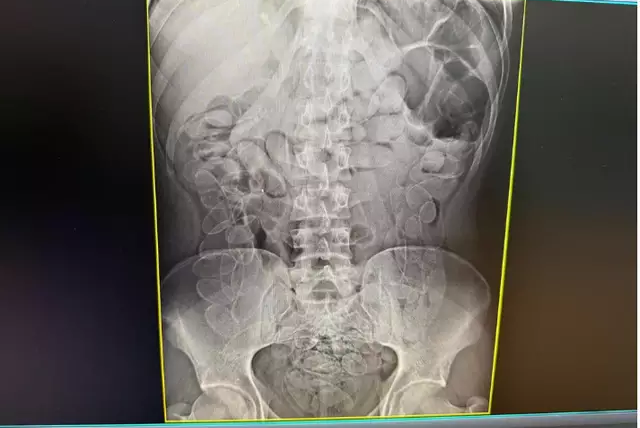

A gravidade da situação foi confirmada por um exame de raio-X abdominal, que revelou múltiplos invólucros alojados no trato digestivo da mulher.

Raio-x mostrando cápsulas de cocaÃna no estômago. (Foto: Divulgação)